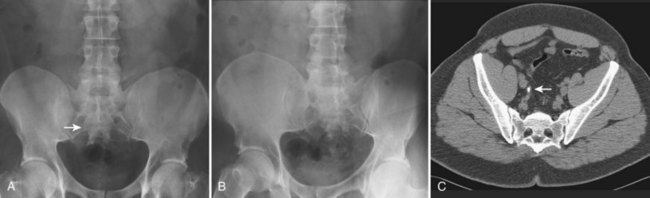

Figure 4–4 A, Right ureteral calculus (arrow) overlying the sacrum is difficult to visualize on the plain film. B, The right posterior oblique study fails to confirm the location of the ureteral calculus. C, Computed tomography confirms this 6-mm calculus in the right ureter at the level of the third sacral segment.